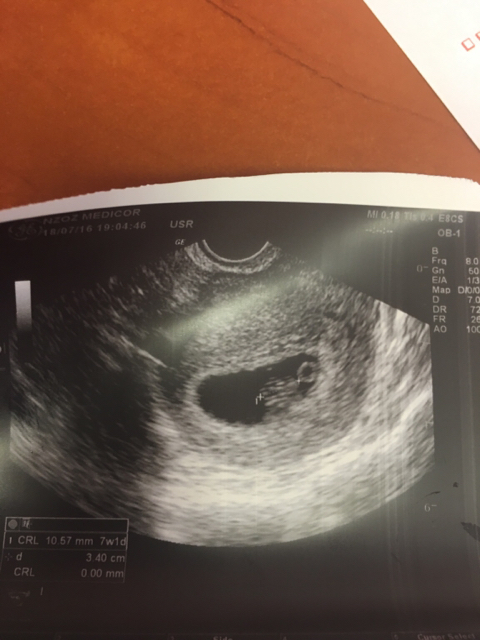

Jestem jestem :) troche sie zeszło miałam normalna wizytę No i wracałam bezpiecznie powoli :) wszystko ok, jest serduszko wg usg 7t1d wg om 6t5d, mam juz kartę ciazy i skierowanie na wszystkie badania łącznie z przeciwciałami odpornosciowymi bo ja mam minusowa grupę krwi. Takze jestem szczęśliwa. Ochrzan dostałam za to ze wzięłam Apap a miałam tylko 37.3 temp ;)